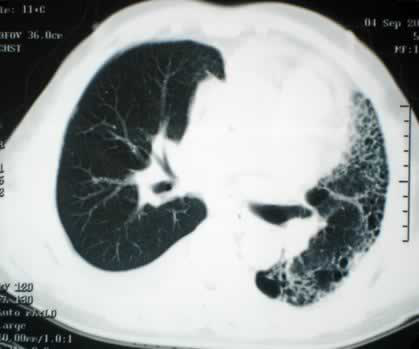

本周养生重点:霜降之后咋养生 保暖养胃是关键